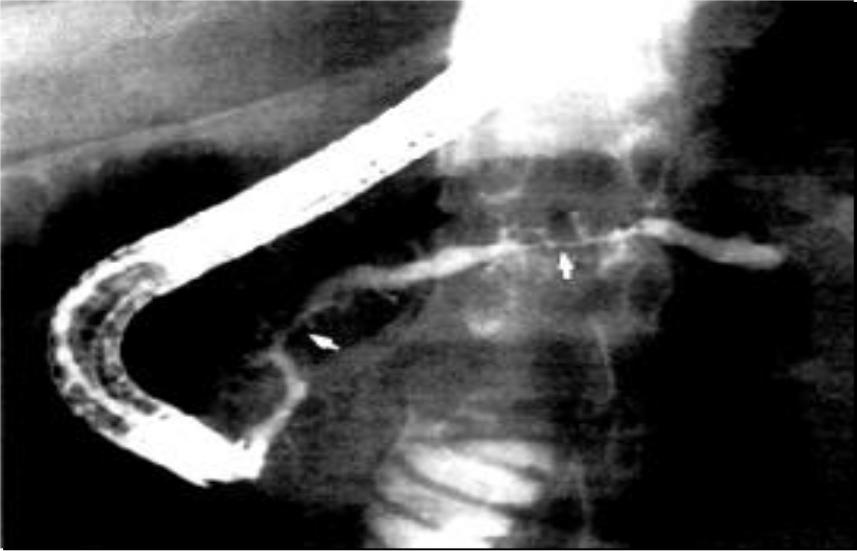

12)ЭРПХГ - эндоскопической ретроградной панкреатохолангиографии, данный метод значительно повысил точность диагностики ХП и расширил лечебные возможности.

Эндоскопическая ретроградная панкреатохолангиография:

Увеличение

интрапанкреатического давления вследствие стеноза протоков ПЖ

Две области выраженного сужения основного протока ПЖ, с последующим постстенотическим расширением